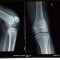

Pemeriksaan penunjang awal yang dapat dilakukan untuk memastikan penyebab terjadinya red flags pada penderita sindrom nyeri patellofemoral adalah rontgen patella. Rontgen diperlukan pada pasien dengan red flags dan yang memenuhi kriteria Ottawa. Pada rontgen dapat ditemukan adanya fraktur, dislokasi, maupun tanda umum bursitis seperti edema.[2]

Salah satu sistem skoring yang dapat digunakan untuk menentukan perlu tidaknya rontgen adalah Ottawa knee rules. Apabila pasien mengalami salah satu dari lima poin ini, maka pemeriksaan rontgen dinilai perlu dilakukan. Kelima poin tersebut meliputi usia 55 tahun ke atas, nyeri lokal pada patela, nyeri pada kaput fibula, tidak dapat fleksi 90 derajat, atau tidak dapat menahan berat badan saat mobilisasi sebanyak empat langkah.[3]